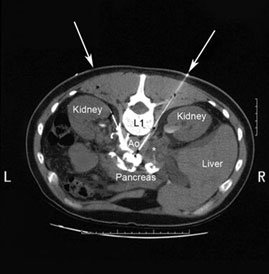

Celiac plexus blocks are procedures of pain management by injecting medication that helps to relieve abdominal pain, mostly due to cancer or chronic pancreatitis.

The celiac plexus is a bundle of nerves that surrounds the abdominal aorta. Blocking these nerves by injecting medicine will aid patient with relief in pain and give better quality of life.

First, an intravenous medication is given to relax the patient and asked to lie on prone position on an x-ray table. The Interventional radiologist will numb an area of skin on back of patient with a local anesthetic. Then, guided by an x-ray, he or she will:

- Insert a thin needle into your back, next to spine, and inject anesthetic

- Insert a second needle on the other side of spine

- Inject dye to confirm that medication will go to the correct spot

- Inject pain medication, such as epinephrine, clonidine or steroid; alcohol or phenol also may be injected to destroy the nerves